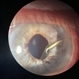

- Traumatic Lens Dislocation

- Traumatic lens dislocation, extraocular